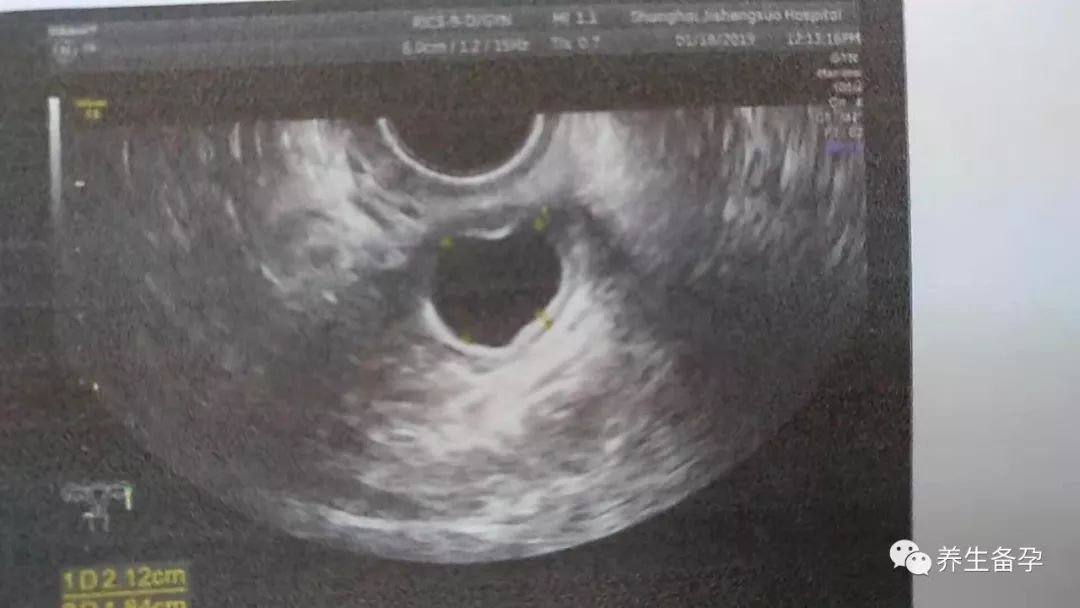

下面给大家看看卵泡质量比较好的照片。